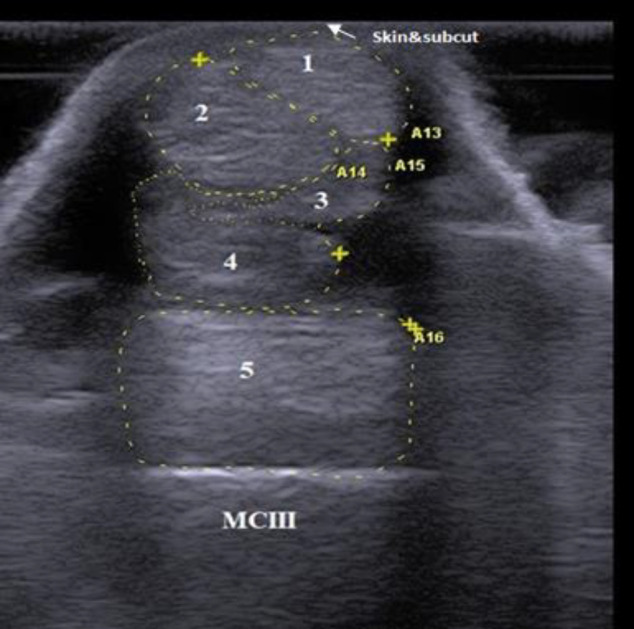

Methods: B-mode ultrasonography was conducted for the proposed tendons and ligaments in 12 clinically normal donkeys. Targeted structures were examined using transverse and longitudinal scans and evaluated in shape, echogenicity, echogenic pattern, fiber alignment pattern, and cross-sectional area (CSA).

Results: Using transverse scan, the sonographic shapes of tendons and ligaments of metacarpal and metatarsal regions were determined. Upon examining different levels of each region, specific ligaments, not tendons, were present only at the higher levels. The echogenicity of ligaments and tendons was either similar or variable across different levels. All tendons and ligaments displayed homogeneous echogenicity except for the suspensory ligament. In the longitudinal scan, tendons maintained linear and parallel fiber alignment along examination levels. Conversely, ligaments displayed mostly inconstant fiber patterns (linear/crimp). There was a statistically significant (P<0.05) difference in CSA of tendons and ligaments between certain levels within metacarpal and metatarsal regions. Upon comparing metacarpal and metatarsal regions, there were distinct variations in some ultrasonographic characteristics of the same tendons and ligaments.